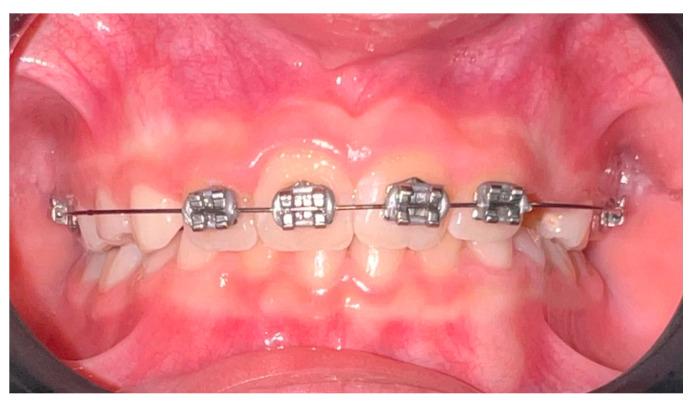

BACKGROUND/OBJECTIVES: This systematic review examines the effectiveness and clinical indications of the 2 × 4 fixed orthodontic appliance for interceptive treatment in children with mixed dentition, aiming to simplify future orthodontic needs.

The 2 × 4 fixed orthodontic appliance is an effective interceptive therapy for mixed dentition. Clinicians can optimize outcomes by understanding its biomechanics and clinical applications. Further research is needed to understand long-term impacts and improve efficiency.

背景/目的:本系统评价旨在探讨2×4固定正畸矫治器对混合牙列期儿童进行阻断性治疗的有效性和临床适应证,以期简化未来的正畸需求。

2×4固定正畸矫治器是一种有效的混合牙列阻断性治疗方法。临床医生可通过了解其生物力学和临床应用来优化治疗效果。需要进一步研究以了解其长期影响并提高效率。